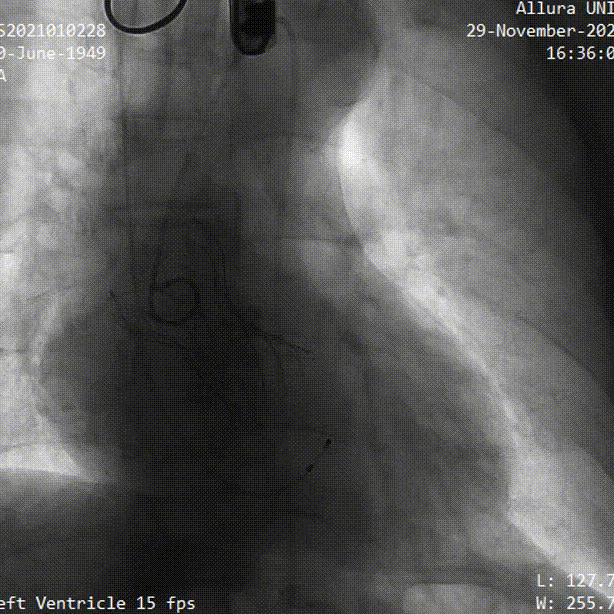

手术过程概览:

术后造影

术后即刻评估

术后压差从104mmHg降至10mmHg,无瓣周漏,瓣膜正常工作,血流动力学即刻得到改善。术后第13小时,患者下床活动。